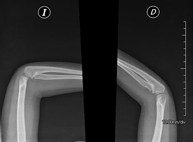

- Osteoarticular

- Limb X-ray

This technique uses X-ray imaging to examine the limbs, especially the bones. Indicated for: trauma, joint infections.